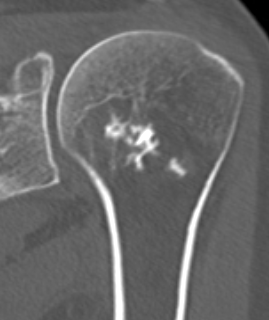

CT Scan

Endosteal scalloping

Large, central enchondroma

- deep endosteal scalloping (>2/3 cortical thickness)

- cortical destruction